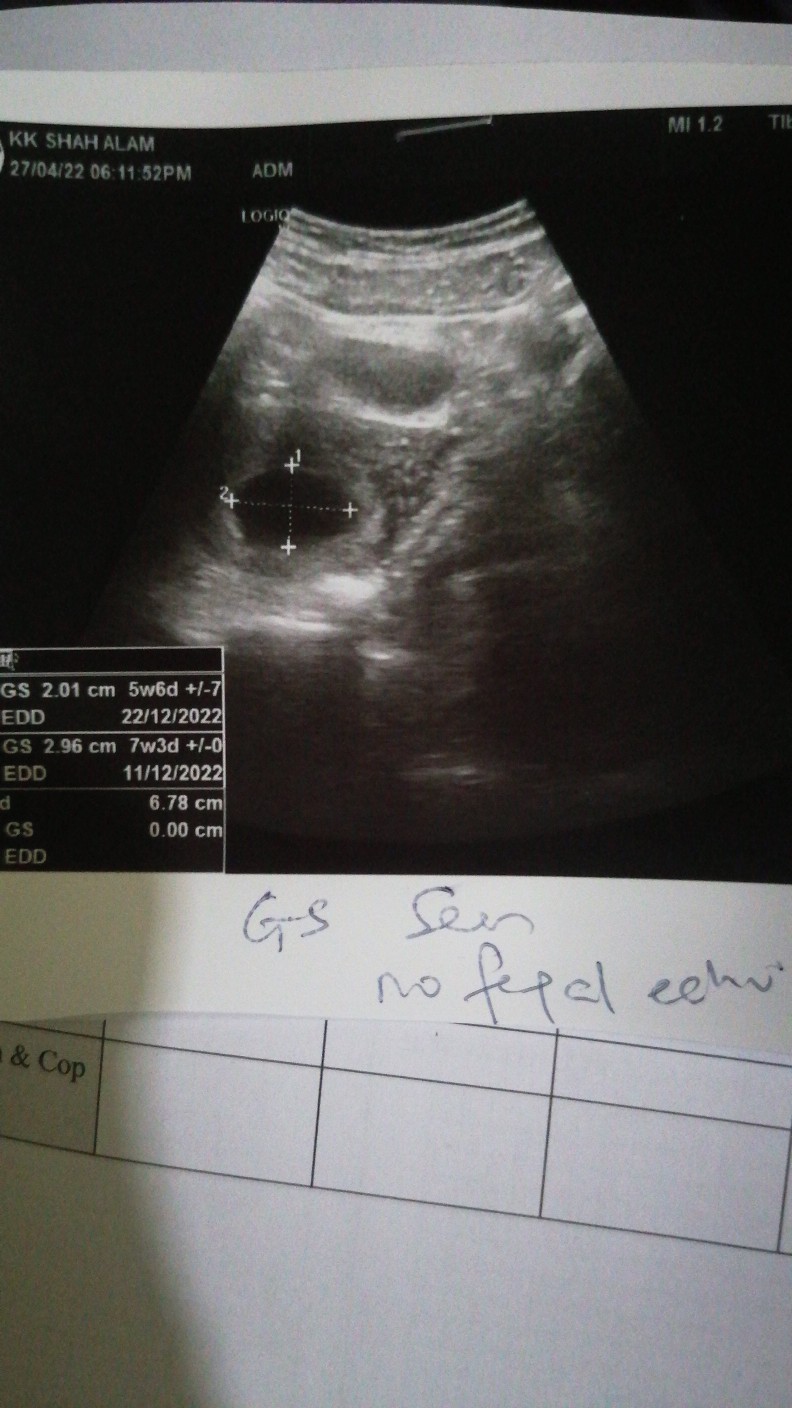

Hi mommies nk tny ada sesiapa tahu tk klinik yg okay utk scan baby area shah alam or subang jaya? Sbb masa 7weeks saya pegi klinik siti utk buka buku bila doktor scan hanya ada kantung sahaja, tk ada hearbeat so doktor refer saya ke hospital tpi bila bgitau mak dan mak mertua diaorg x bgi saya pegi katanya takut dri tk gugur nnti gugur. Saya xde bleeding or apa2 skrg saya dh 9weeks jumaat nnti bru nk gi kk buka buku pink. #firstmom #pleasehelp